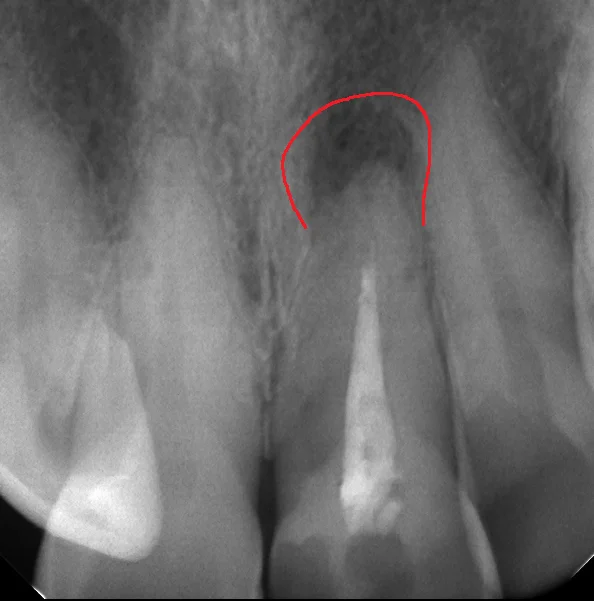

神経の治療がダメになるとどうなるかというと、画像の赤で囲まれている所のように根の先に膿が溜まってきます。

根の先に膿が溜まった状態で長期間放置することで、根管(神経の管)内に限局していた感染源が根管の外に出てしまい、そこで巣を作ることがあります。

そうなると神経の治療でどれだけ根管内を綺麗にしても、原因は根管の外に出ているので治りません。

なので、レントゲン上で膿が認められて、担当医から「治療した方が良い」と言われた場合は早めに治療に入った方が無難です。